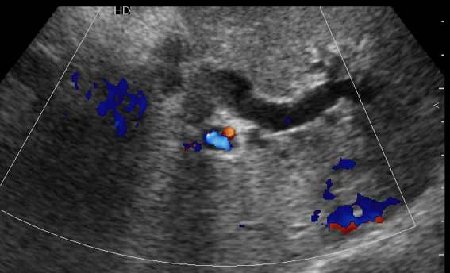

Дело в том, что в холедохе имеется нечто изоэхогенное (не знаю, видно ли это нечто на ваших мониторах). Врач УЗИ при осмотре перед поступлением в стационар на основании этой картины в заключении отметил возможность опухоли холедоха.

Гнойный холангит на фоне обструкции БДС конкрементом (камень вне скана). В холедохе определяется желчь с осадком, которая может быть ошибочно принята за его опухоль.